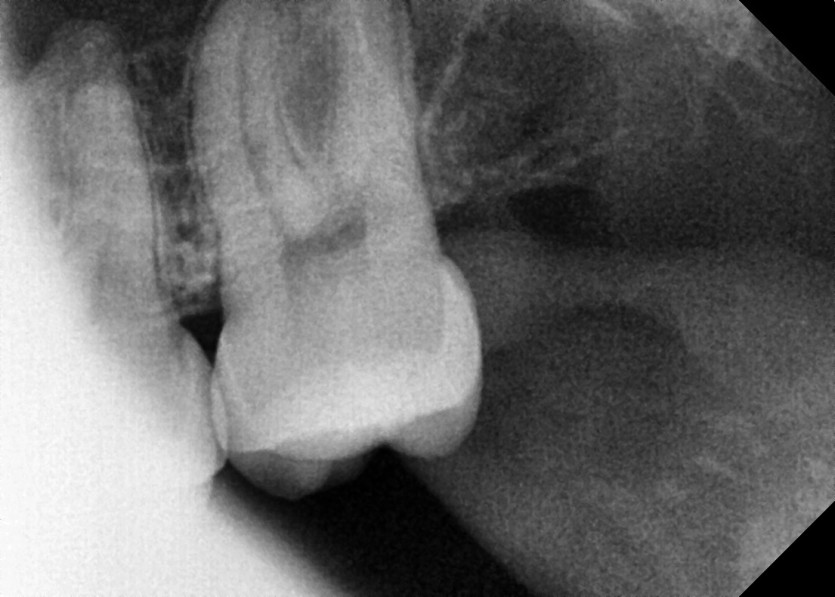

#28 사랑니 발치

구강 외과 전문의가 당일 발치했습니다.-----------------------------------------------------------------------------------------------------------------------------------